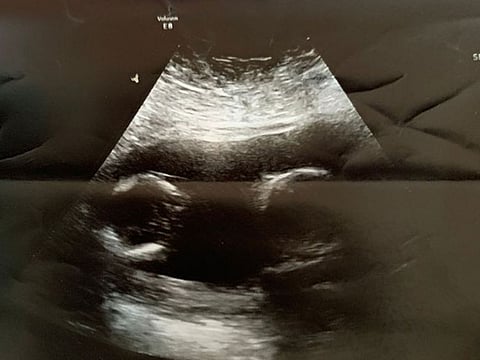

She’s held on to that black-and-while photograph of the twins swimming in her womb. It was a 12-year wait before their introduction and she’s rather fond of the memento. Gulf News reader Shamila H knew she wanted to have babies, but she had suffered from polycystic ovary syndrome (PCOS), which wouldn’t cause infertility but would interfere with ovulation making it difficult.

“Things were just out of control with for me and my husband. And so then we were just no time for cooking. No time for planning. We were just ordering from outside,” she laughs, already planning a return to keto in a few months. For now though, the world centres around her babies – who’ve gone from 2D blurbs on a much-awaited sonogram to animated 3D colourful pops of joy.